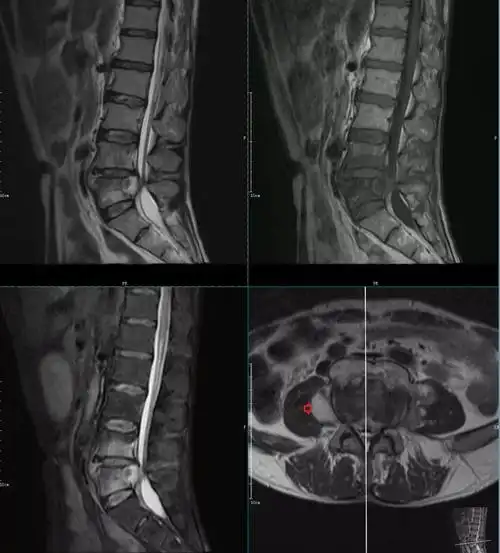

椎体终板炎发生机制分型以及mri表现